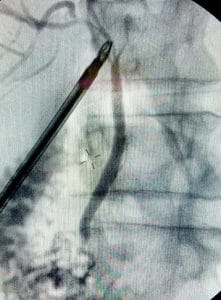

X-ray of the bile ducts taken during an operation

X-ray of the bile ducts taken during an operation.

It allows for the main bile ducts to be visualised, thereby checking for any anatomical/pathological variation of the biliary system as well as ensuring that gallstones have not passed out of the gallbladder and into the main bile ducts.